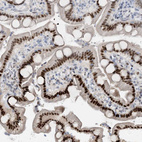

Immunohistochemical staining of human salivary gland shows strong nuclear positivity in glandular cells in addition to weak cytoplasmic positivity.